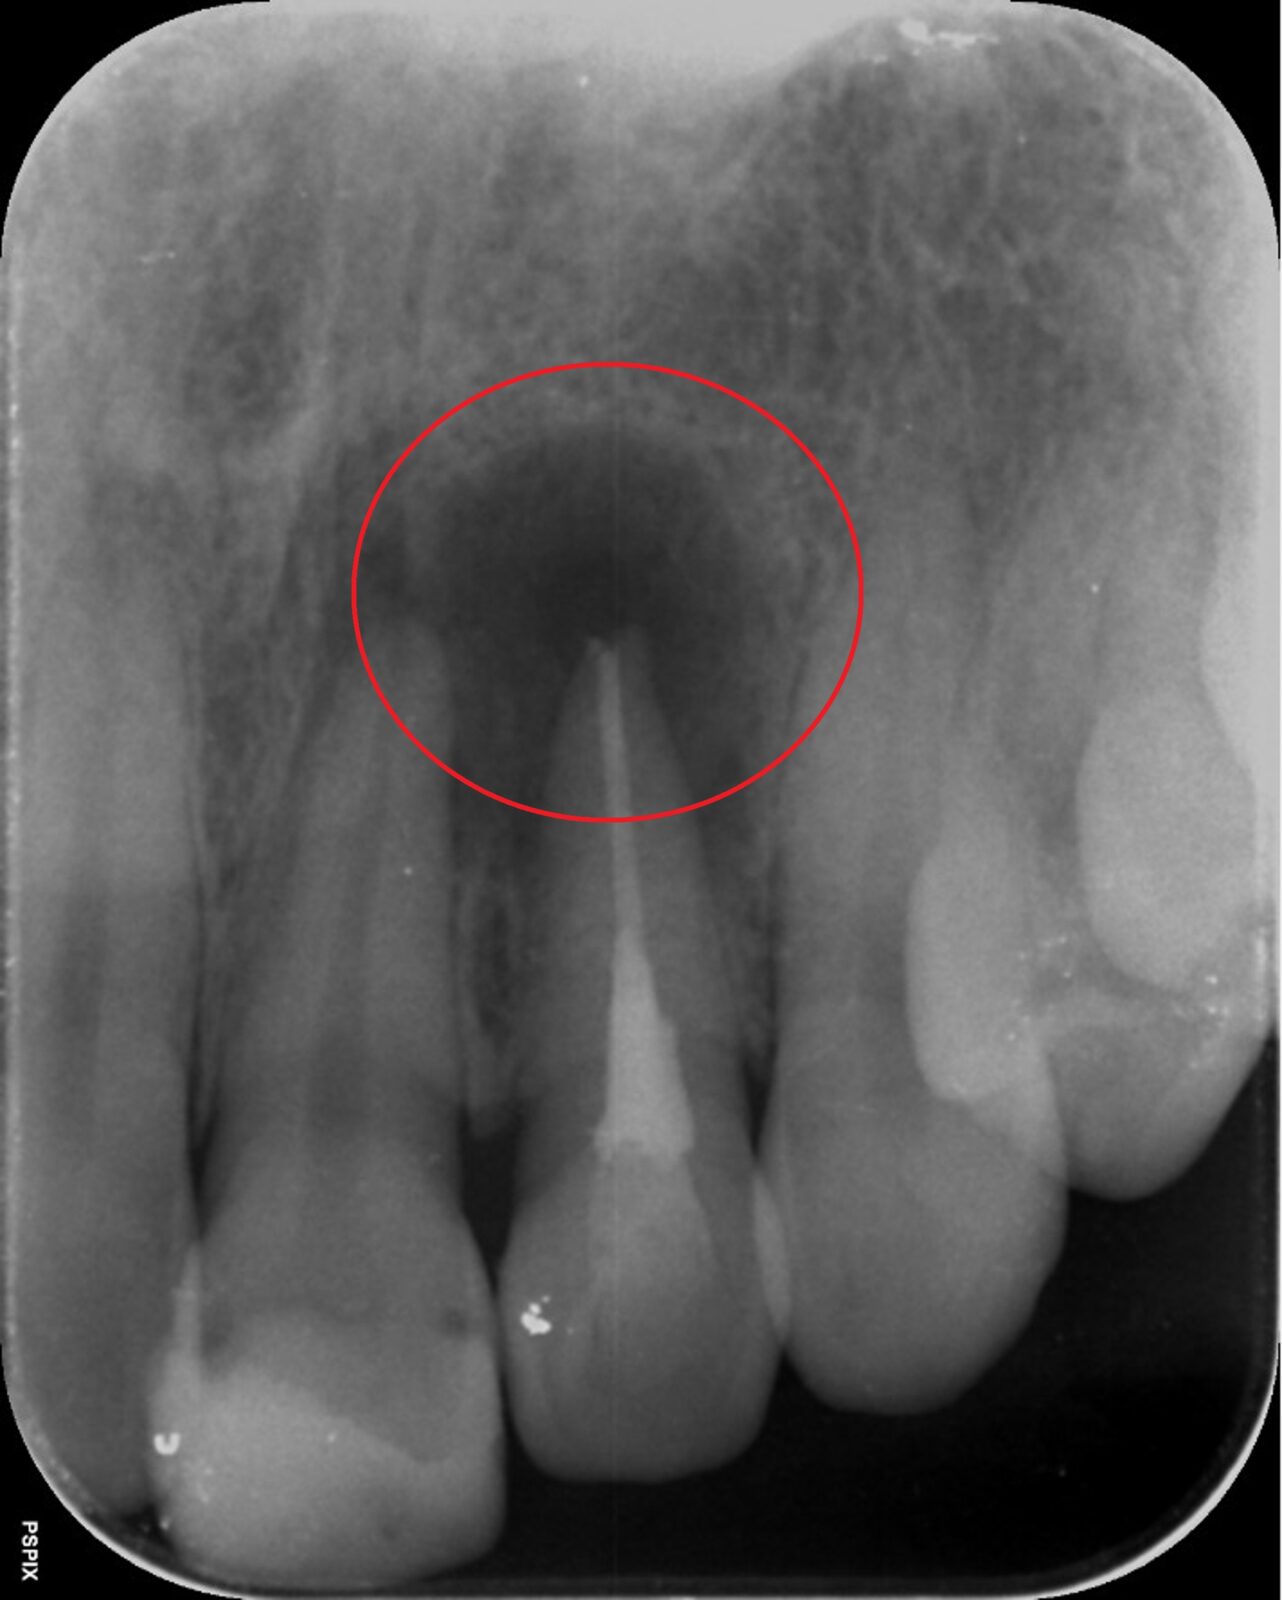

次の画像は、同じ患部をCTとレントゲンで撮影した画像です。

• 比較

「左」の写真がCTで、「右」の画像がレントゲンで撮影したものです。

赤丸で囲んだところには、黒い影が見えます。ここには炎症が起こっているのですが、右の写真には影がありません。つまり、2次元のレントゲンだけで診断した場合、問題のある部分は治療しない選択をするため、最終的には抜歯の運命をたどるケースです。